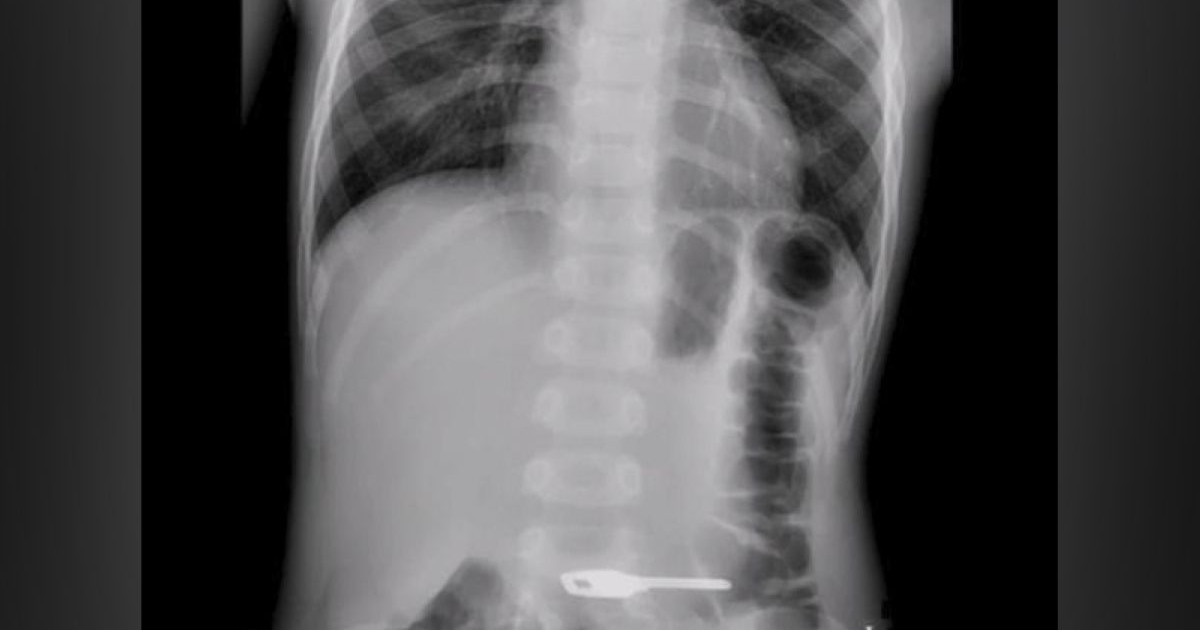

Ақтауда бес жасар баланың ішінен кілт шықты Ақтауда 2015 жылы туған баланың ішінен үйдің кілті алынды, – деп жазды ҚазАқпарат. Облыстық балалар ауруханасының хирургы Орынбай Жалбайұлының және «SOFIE MEDGROUP» клиникасының эндоскопист дәрігерінің бірлесе отырып жасаған жұмысының арқасында 5 жасар балаға ота жасалып, оның ішінен кілт алынған. Ата-анасының айтуынша, кілт баланың ішінде 10 күндей болған. Қазір баланың жағдайы бірқалыпты.